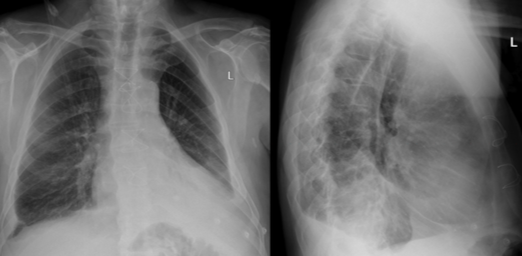

33yo female presents with dyspnoea on exertion with associated cyanosis and fatigue. On examination she has a loud P2. Over the following years, she goes on to develop RVF

Pulmonary HTN

Causes: idiopathic (primary), PE, COPD, ILD, LVF, connective tissue disease, portal hypertension